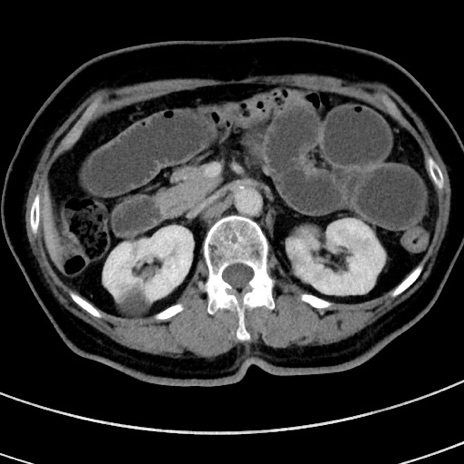

症例9(横断像)

【症例】 60歳代女性

【主訴】むかつき、みぞおちの痛み

【現病歴】3日前よりむかつきがあり、食事がとれない。

【既往歴】糖尿病

【身体所見】発熱なし、心窩部圧痛軽度あるも、腹膜刺激症状なし。

【データ】WBC 7400、CRP 1.92